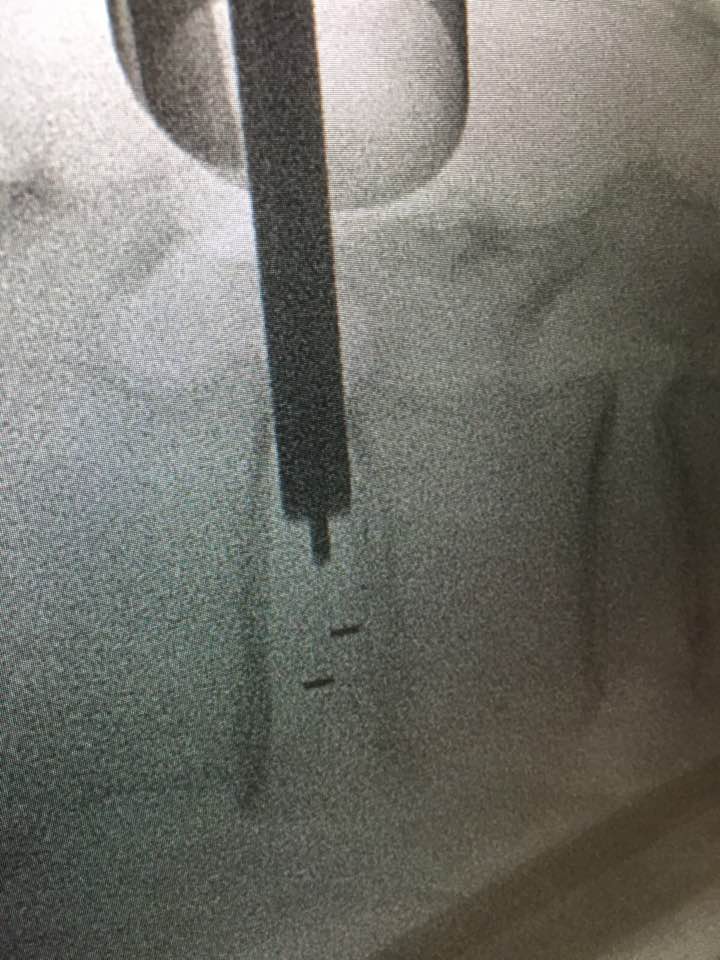

Lumbar intervertebral foramina epidural nerve root injection

After injecting spinal nerve roots with anesthesia, confirming the cause of spinal sciatica symptoms. I can tell the patient whether lumbar screw fusion is helpful.